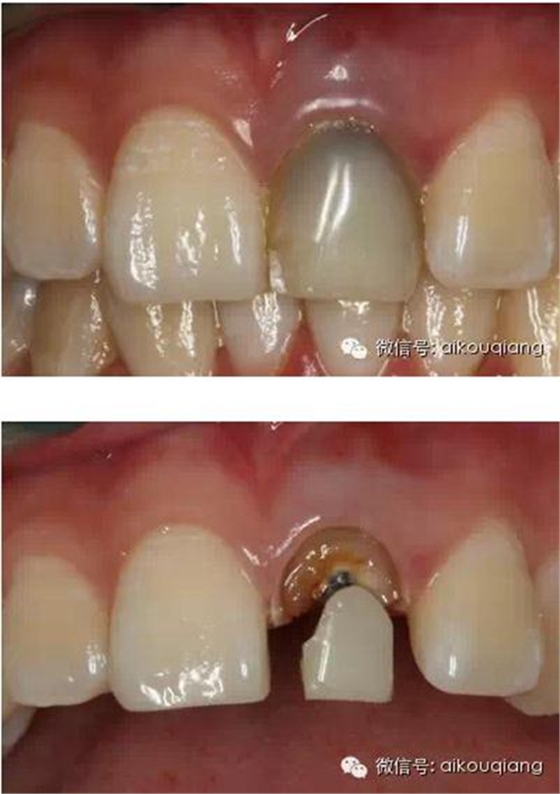

患者外院螺紋樁核加樹脂冠

唇側(cè)出現(xiàn)瘺管